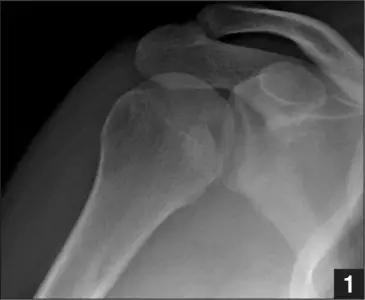

肩关节脱位时,肱骨头和关节盂发生撞击,肱骨头表面凹陷性骨折。

肩关节前脱位时发生的肱骨头后外侧凹陷性骨折,是经典的 Hill-Sachs 损伤(Hill-Sachs lesion);

而肩关节后脱位时发生的肱骨头前内侧凹陷性骨折,是反 Hill-Sachs 损伤(Reverse Hill-Sachs lesion/ McLaughlin lesion)。